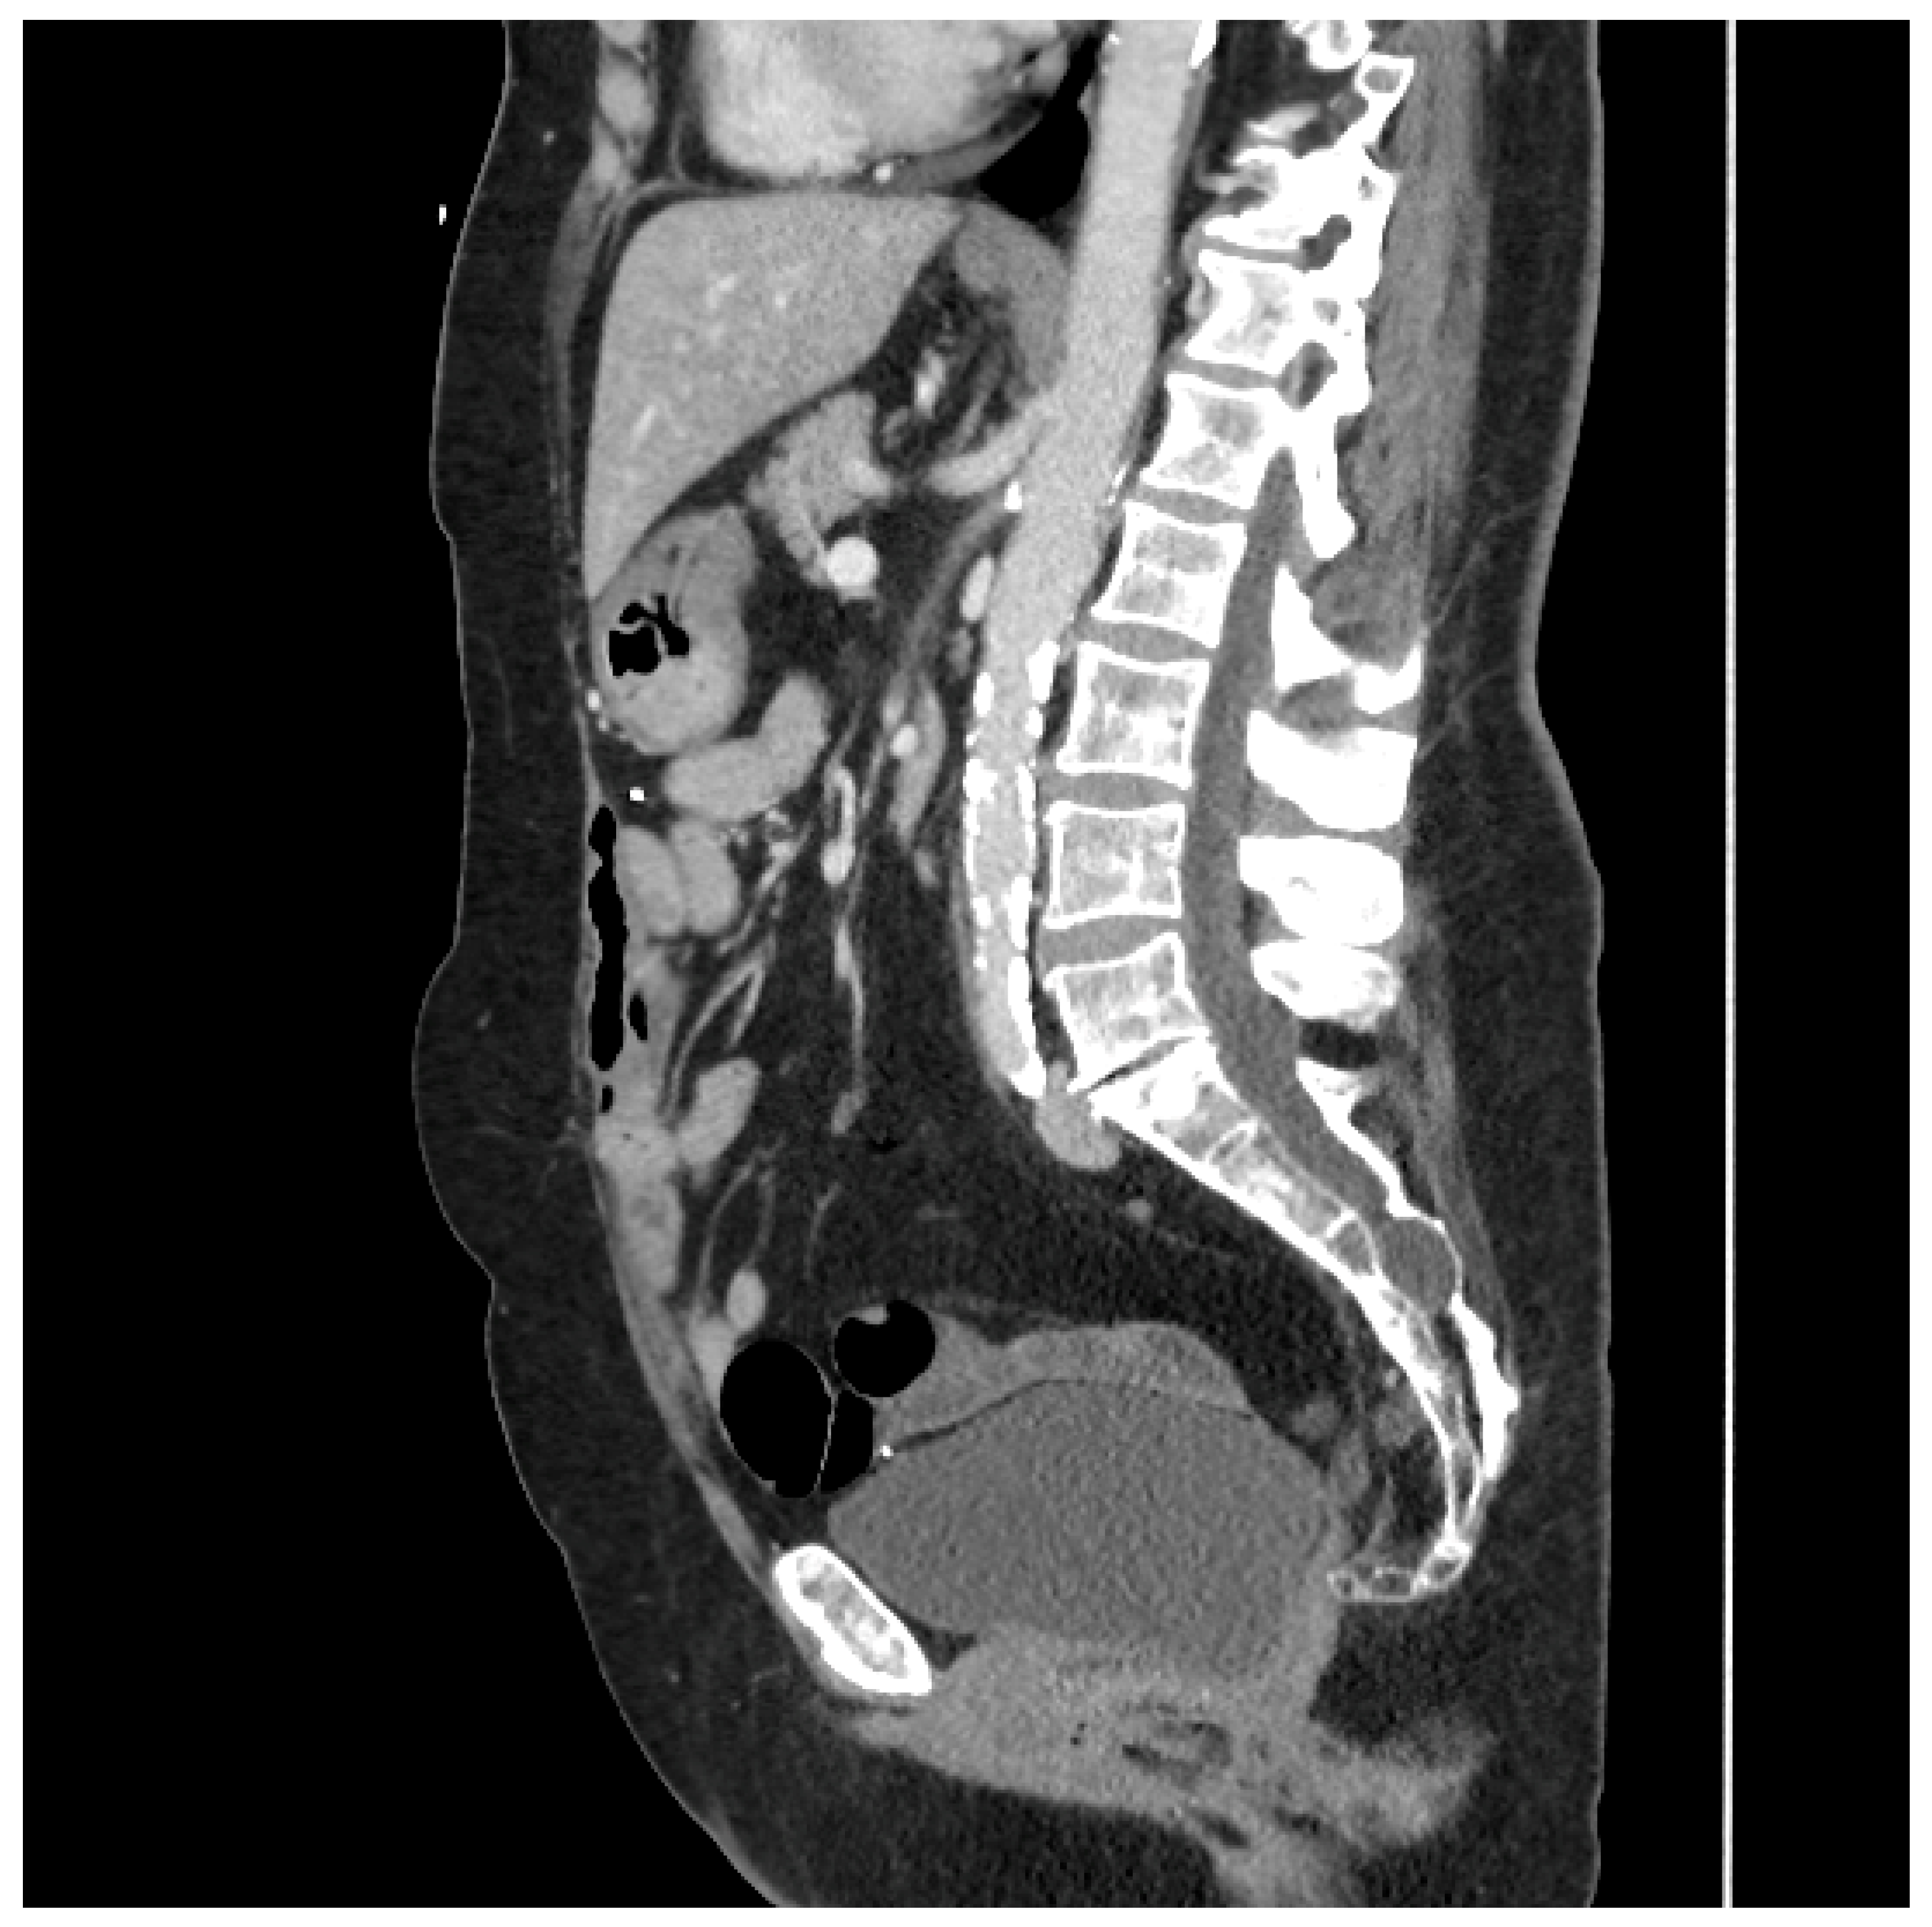

3.1. Sigmoid Mesocolic Flaps

This type of flap was used in two patients. The first underwent total proctocolectomy for fistulizing perianal disease and a rectovaginal fistula. She had a diminutive greater omentum found during surgery that was deemed unsuitable for an omental pedicle flap. Close colonic and rectal dissection were carried out, which left a sufficient amount of sigmoid mesocolon in situ. The sigmoid mesocolon was advanced inferiorly and sutured to the pelvic brim to close it off and prevent the small bowel from entering the pelvis. The blood supply of the mesocolon was preserved as the inferior mesenteric artery was not ligated, and the superior rectal artery was left intact. A 15 Fr drain was left in the pelvis at the end of the operation. A CT scan performed four years after surgery demonstrated the resilience of this flap and its prolonged ability to prevent the small bowel from adhering to the proctectomy resection bed (See Figure 2).

Figure 2.

Sagittal CT scan performed four years after proctocolectomy and sigmoid mesocolic flap. The mesocolic flap is seen here filling the pelvis and adherent to the back of the bladder, forming a sling-like configuration, thus preventing the small bowel from adhering to the proctectomy resection bed in the pelvis. (Used with permission from the Mayo Foundation for Medical Education and Research; all rights reserved).